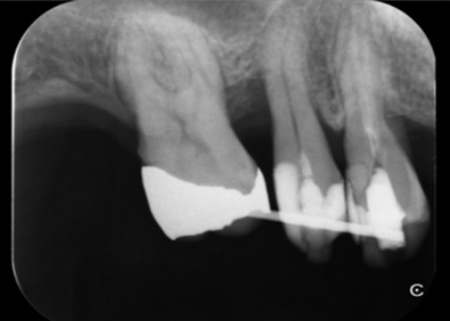

そこでまず、根管内を無菌的に清掃して感染源を取り除く精密根管治療と、歯ぐきの上や中に付着した歯石・細菌を除去し、炎症を改善する歯周治療を行います。

その後、失われた骨の回復を目指す再生療法を併用する方針としました。

再生療法では局所麻酔を行い、歯ぐきを慎重に開いて歯の根の表面を露出させました。

歯ぐきの奥深くに付着していた歯石をしっかり除去し、根の表面を滑らかに整えたあと骨の再生を促す材料を使用し、歯ぐきを元の位置に戻して縫合しました。

右下の奥歯3本についても同様に、再生療法を行いました。